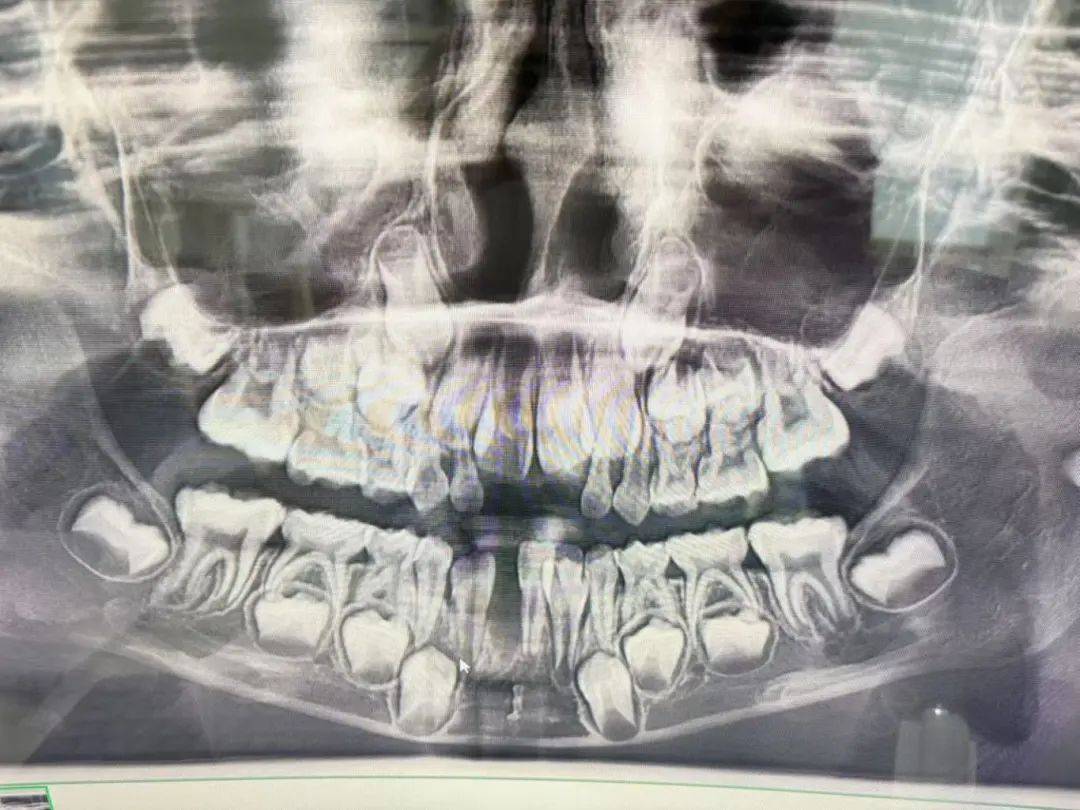

“这颗牙很难拔,拔了很长时间,最后医生拿出来的牙齿是很长的一颗,为此,我觉得很奇怪。孩子告诉我,拔牙后很疼。”孟女士说,医生随后带着孩子去照了一个片,并告诉她,孩子天生缺失恒牙,对此她也不太懂。

孟女士说本来孩子要拔的是右边牙齿,结果医生却把中间的恒牙拔了。

回到家,孟女士一想到女儿没有恒牙一事,就着急不已,于是又带着女儿去了云南省第一人民医院进行检查,这才发现女儿被拔掉的就是恒牙,并非天生缺失。由于当天已晚,孟女士只能带女儿先回家休息。

记者从孟女士提供的两张照片上看到,第一张照片上的牙齿是完整的,第二张照片上则有一颗牙不见了,而应该拔掉的那颗牙还在。